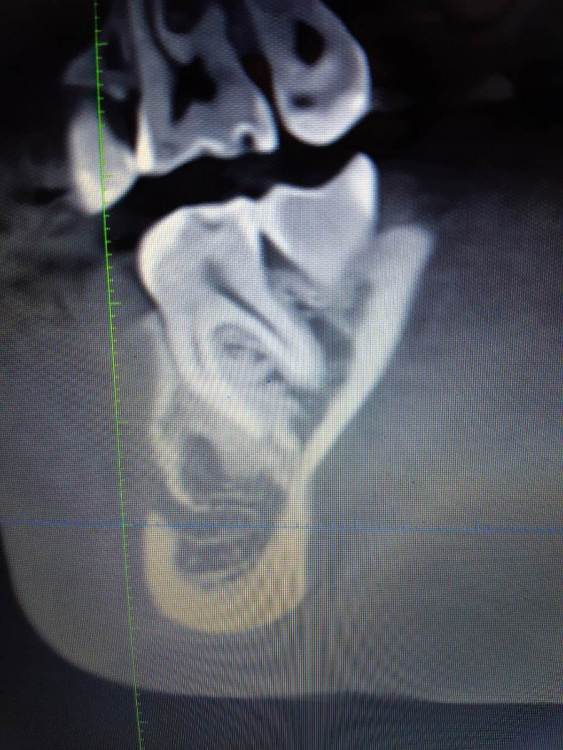

Коллеги, помогите советом что это может быть. Ничего не беспокоит, найдено случайно. Есть бруксизм, пат.стираемость, гнатолог считает что было неправильное ортодонтическое лечение.